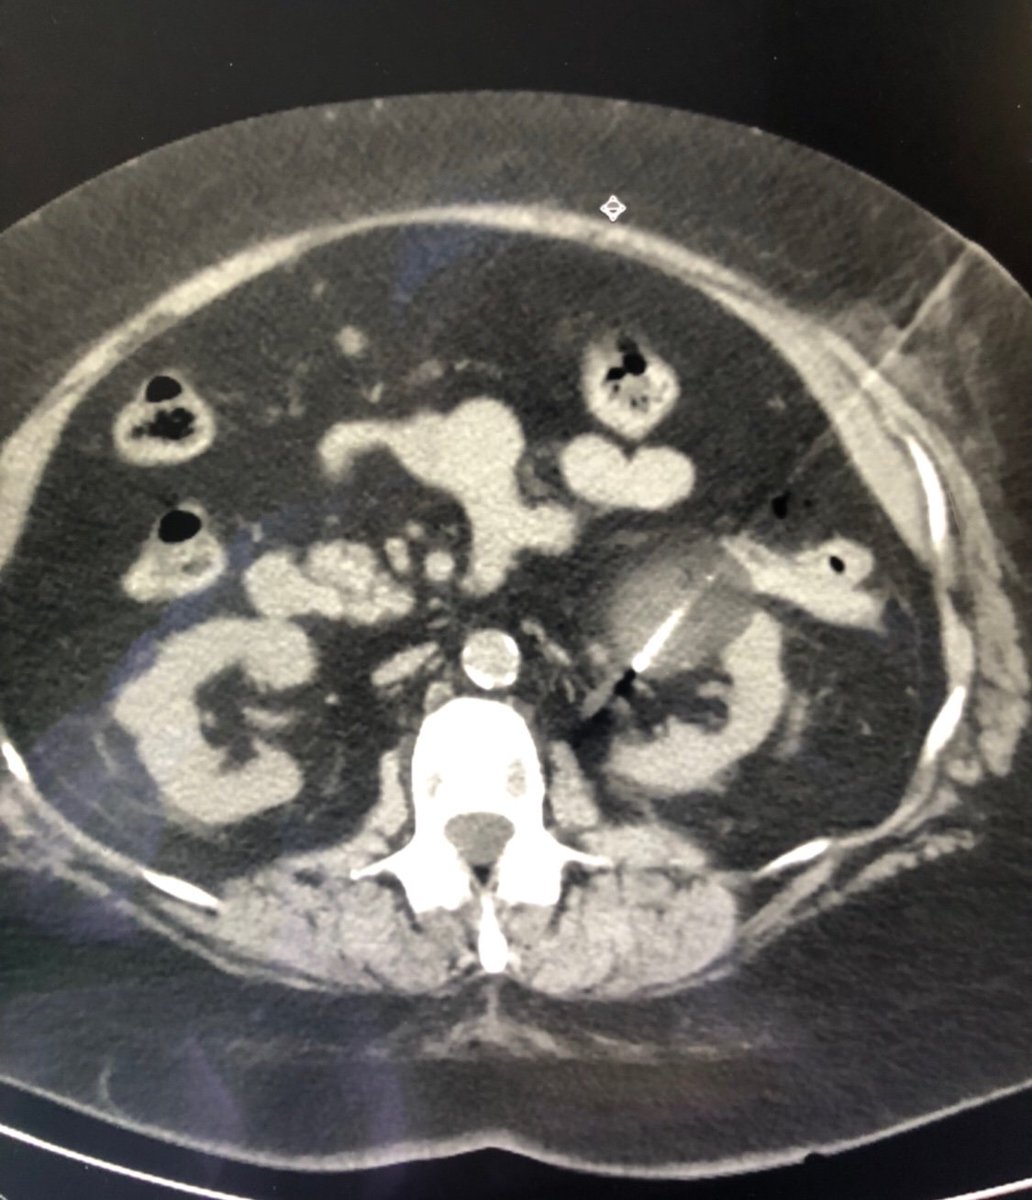

New study @AnnalsofIM bit.ly/2Km3KYu by @DrTalenfeld @WeillCornell: Percutaneous ablation for T1a #renalcancer has similar 5-year survival rates to radical nephrectomy but with far fewer 30-day complications and less #kidneyfailure.